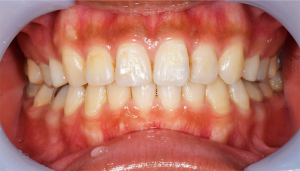

歯石除去

治療前

治療後

| 年齢 | 36歳・男性 |

| 主訴 | 歯石をとりたい |

| 治療内容 | 歯石除去 |

| 治療期間 | 30分 |

| 費用 | 約2,000円 |

| リスク・副作用 | ・歯ぐきの炎症が強いと歯石を取る際に出血することがあります。 ・処置後に歯がしみることがあります。 ・歯と歯の間に隙間ができるので、息が漏れ発音しにくいと感じることがあります。 ・歯ぐきの炎症が軽減すると歯ぐきが引き締まり、歯が長く見えることがあります。 |